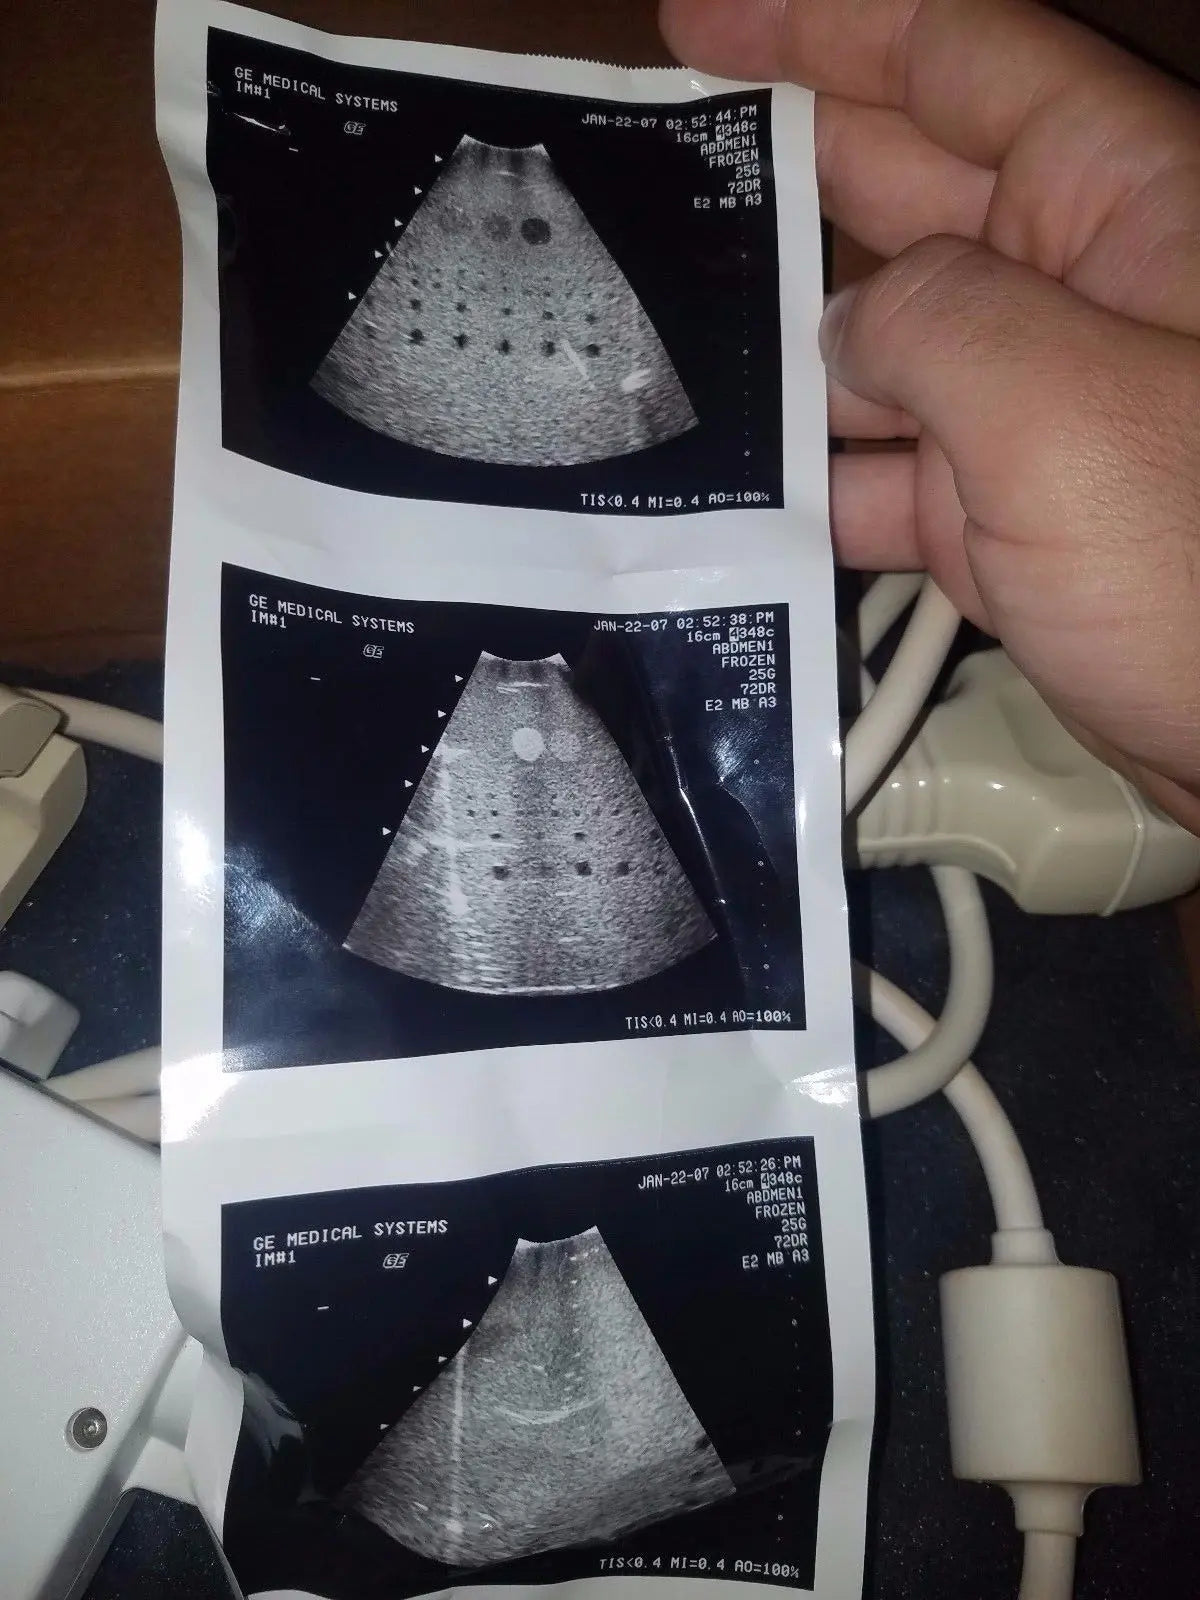

DIAGNOSTIC ULTRASOUND MACHINES FOR SALE

GE 348c Ultrasound convex ultrasound transducer

Sale price$ 1,439.90

DIAGNOSTIC ULTRASOUND MACHINES FOR SALE

GE 348C 2197480 ULTRASOUND TRANSDUCER PROBE

Sale price$ 3,599.78